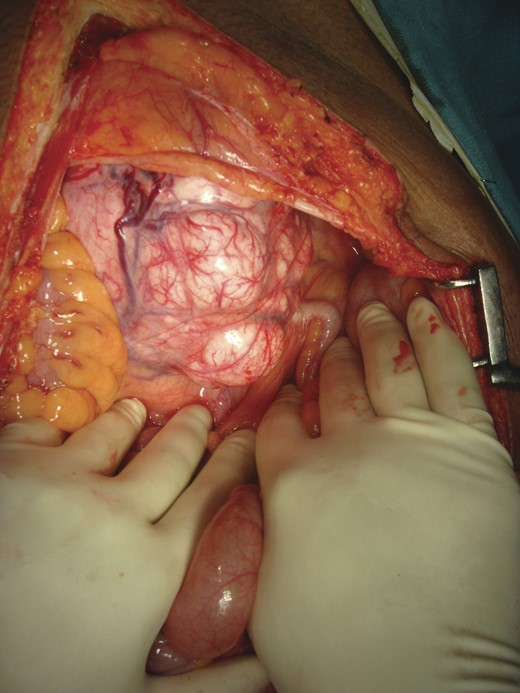

He was maintained on 10% dextrose infusion and subsequently was taken up for laparotomy. There was no visceral, peritoneal or lymphatic metastasis. There was a 20 × 13 cm solid well-encapsulated vascular tumor present in the pelvic cavity posterior to urinary bladder, which was extending above and anterior to the right common iliac vessels. An en bloc excision of the tumor was performed (Figs 3 and 4).

Intra-operative picture: a 20 × 13 cm solid well-encapsulated tumor was present in the pelvic cavity posterior to urinary bladder.